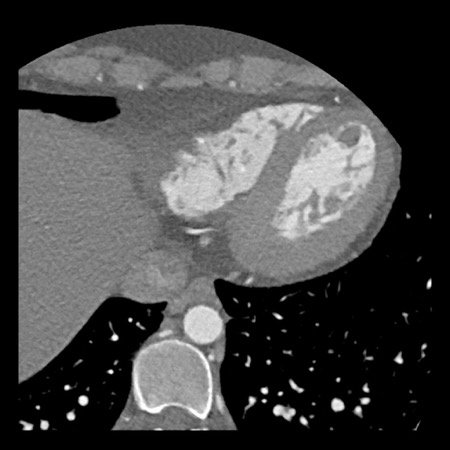

case 3 – Calcium score 0 and severe stenoses.

First, scroll through the CTA images.

How would you describe the findings on the coronary CTA?

The findings are:

- The total calcium

score of 0 indicates the absence of calcified plaque in the coronary

tree. - Severe stenosis

(70-99%) in the mid LAD and D2 branch.